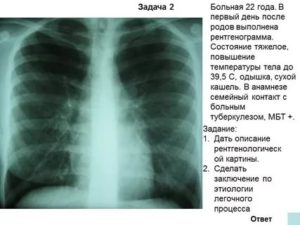

Синдром уплотнения. Очаг низкой и средней плотности. Туберкулез.

Воспалительные заболевания часто дифференцируют с туберкулёзом лёгких. Туберкулома чаще локализуется на верхушках лёгочных полей. Тень округлая, часто с просветлением в центре — очаг деструкции. Наблюдается расширение корней лёгких.

- Туберкулез. При туберкулезе наблюдается сильный воспалительный процесс легочной ткани. На рентгенограмме он выглядит как несколько округлых очаговых теней. Как правило это увеличенные лимфоузлы. Также при туберкулезе легочный рисунок в верхней части усилен.